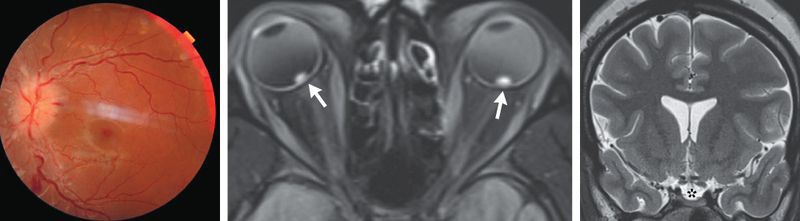

A 25-year-old woman with severe obesity presented to the emergency department with a 1-week history of blurred vision, transient visual obscurations, daily headaches, and intermittent whooshing sounds. Her body-mass index (the weight in kilograms divided by the square of the height in meters) was 57. On neurologic examination, optic-disk swelling and retinal hemorrhages were present in both eyes (Panel A, left eye). The results of visual-field and cranial-nerve testing were normal. Magnetic resonance imaging and venography of the head revealed flattened posterior globes with marked elevation of the optic-nerve heads (Panel B, arrows), an empty sella (Panel C, asterisk), and stenoses of the transverse sinuses without obstruction or thromboses — all of which were suggestive of elevated cerebrospinal fluid pressure. A lumbar puncture was notable for an elevated opening pressure of 55 cm of water (reference range, 10 to 20); the results of the cerebrospinal fluid analysis were normal. A diagnosis of idiopathic intracranial hypertension was made. Idiopathic intracranial hypertension is a disorder associated with obesity that manifests with symptoms resulting from increased intracranial pressure, including headaches, diplopia, visual field defects, and pulsatile tinnitus. Treatment with high-dose acetazolamide was started, and counseling on weight loss was provided. At a 1-month follow-up visit, the patient’s papilledema had decreased, and treatment with acetazolamide had been continued.